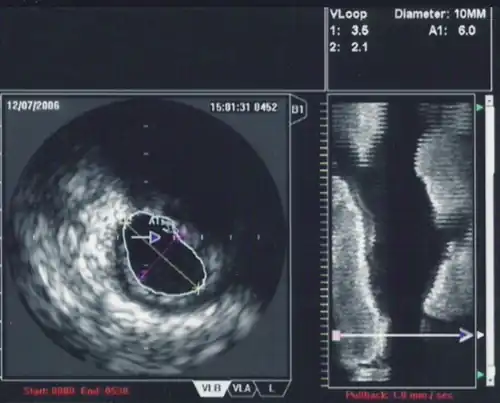

The ultrasound catheter tip is slid in over the guidewire and positioned, using angiography techniques so that the tip is at the farthest away position to be imaged. The sound waves are emitted from the catheter tip, are usually in the 20-40 MHz range, and the catheter also receives and conducts the return echo information out to the external computerized ultrasound equipment which constructs and displays a real time ultrasound image of a thin section of the blood vessel currently surrounding the catheter tip, usually displayed at 30 frames/second image.

The guide wire is kept stationary and the ultrasound catheter tip is slid backwards, usually under motorized control at a pullback speed of 0.5 mm/s. (The motorized pullback tends to be smoother than hand movement by the physician.)

While the routine use of IVUS during percutaneous coronary intervention does not improve short term outcomes,[10] there are a number of situations in which IVUS is of particular use in the treatment of coronary artery disease of the heart. In particular in cases when the degree of stenosis of a coronary artery is unclear, IVUS can directly quantify the percentage of stenosis and give insight into the anatomy of the plaque.

When using IVUS to determine whether an individual's left main disease is clinically significant, in terms of the desirability of physical intervention, the two most widely used parameters are the degree of stenosis and the minimal lumen area.[12] A cross sectional area of ≤7 mm² in a symptomatic individual or ≤6 mm² in an asymptomatic individual[13] is considered to be clinically significant and warrants intervention to improve one-year mortality. However, these exact cutoffs are up for debate and different cutoff cross-sectional areas may be used in practice depending on differing interpretations of the trial data.